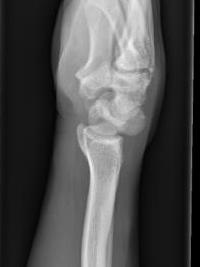

Lateral xray

Distal radius / lunate / capitate: not aligned, spilled teacup

Normal versus spilled tea cup appearance on lateral with spilled tea cup